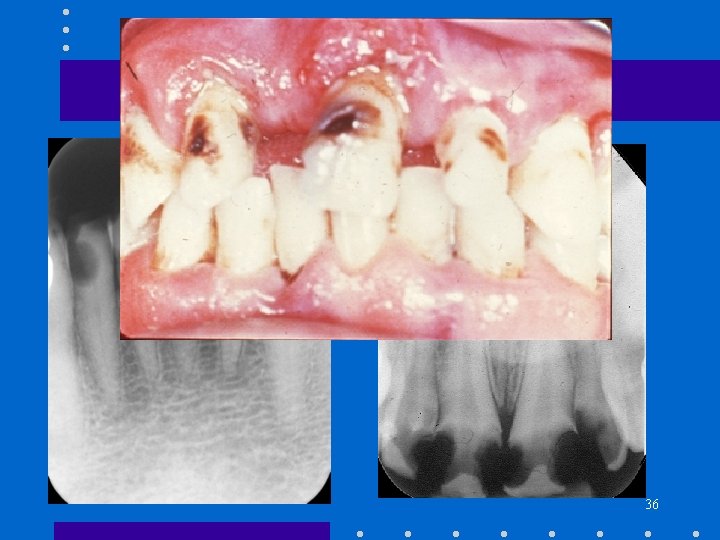

Rampant Caries • • • Children Poor dietary habits Extensive caries Proximal and smooth surface Socio-economic factors 35

Rampant Caries 36